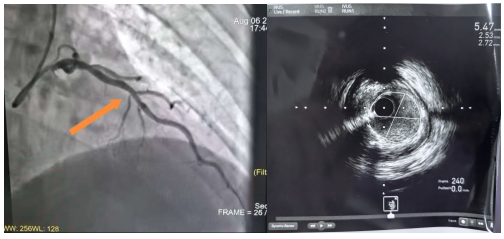

2. 精准干预临界病变:患者冬某冠脉造影提示前降支“临界狭窄”(60-70%),IVUS检查明确管腔面积仅2.82mm²(需介入治疗),支架植入后复查管腔面积提升至5.47mm²,支架贴壁良好,显著提升疗效。

冠脉造影结果 支架前IVUS检查结果

支架后复查造影结果 术后复查IVUS结果